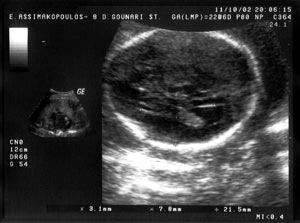

διατομή και πάλι με υπερηχογενή όρια προς τα επάνω και προς τα κάτω. Στην εικόνα

1 παρουσιάζεται απεικόνιση φυσιολογικού μεσολοβίου σε έμβρυο 25 εβδομάδων σε

οβελιαία διατομή. Αργότερα, μετά τις 29-30 εβδομάδες γίνεται ορατό σε οβελιαία

διατομή και το προσαγωγίο, μία τοξοειδής δέσμη λευκής ουσίας με πορεία παράλληλη

με το μεσολόβιο. Επιπρόσθετα, στην ίδια διατομή είναι ορατή και η περιμεσολοβιακή

αρτηρία, στο άνω τμήμα και σε όλο το μήκος του μεσολοβίου.

1.

2.

Eικόνα

1. Aπεικόνιση φυσιολογικού μεσολοβίου σε έμβρυο 25 εβδομάδων σε οβελιαία

διατομή.

Εικόνα

2. Απεικόνιση της απουσίας του μεσολοβίου στην περίπτωση 1, σε οβελιαία

διατομή (σύγκρινε με εικόνα 1).